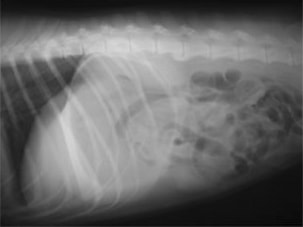

術後レントゲン

腹部臓器が腹腔内に戻り、腹部と胸部の境界および心臓や肺の陰影が明瞭に見えるようになりました。